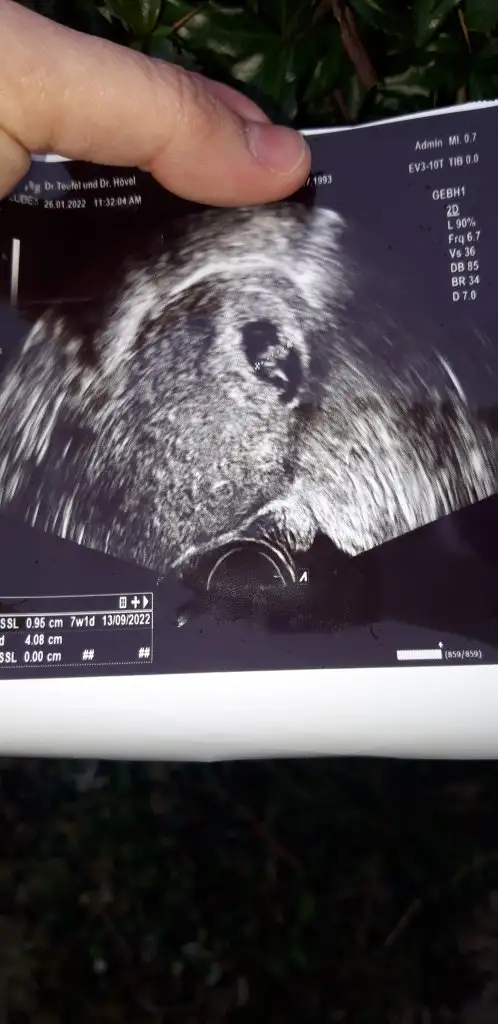

nubu belli degil galiba enterasn ben ultrasonda hem yukarida gordum hem paralel ama foto yok😀